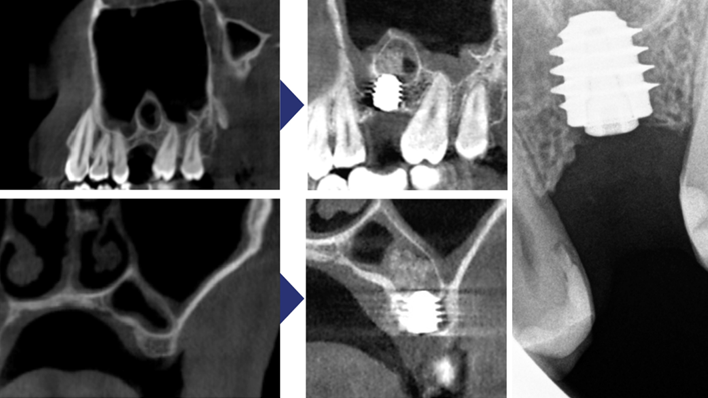

Clinical case: Installation of dental implants in complicated anatomic conditions using crest lifting methods

- Courtesy of Dr.Alexander Lysov, Russia -

AnyRidge, complicated anatomic conditions, crest lift, MICA Kit, Dr. Alexander Lysov, bone regeneration, GBR, #26, maxillary posterior

AnyRidge implant system, MICA Kit